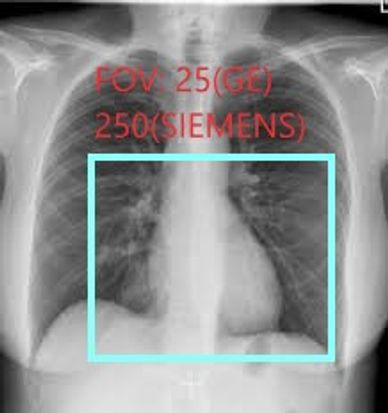

ONCE IV HAS BEEN PLACED, POSITION PATIENT WITH BOTH ARMS UP AND PERFORM A ROUTINE CARDIAC CALCIUM SCORE. REMEMBER TO KEEP YOU FIELD-OF-VIEW (FOV) TO 25CM FOR GE OR 250MM FOR SIEMENS

A FOV OF 25(GE) 250(SIEMENS) IS REQUIRED FOR SOFTWARE TO POST PROCESS